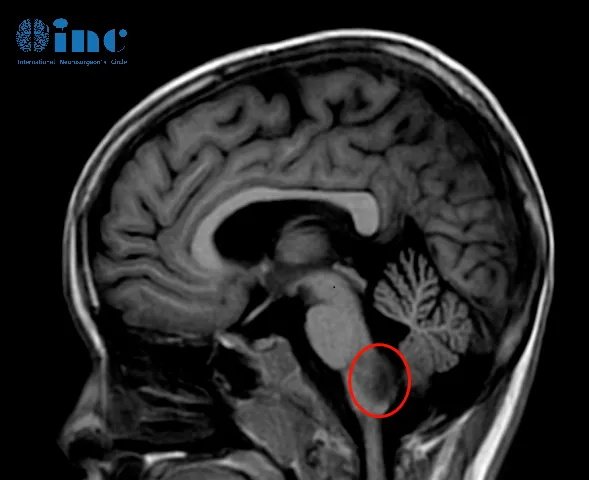

术前核磁影像

占位所处位置在人体的“生命中枢”脑干-延髓之上,延髓控制着人体的吞咽、呼吸等基本功能。

2022年08月25,常规核磁复查,结果提示肿瘤进展,延髓右部不规则肿胀范围约2.6cmX2.5cmX2.3cm。